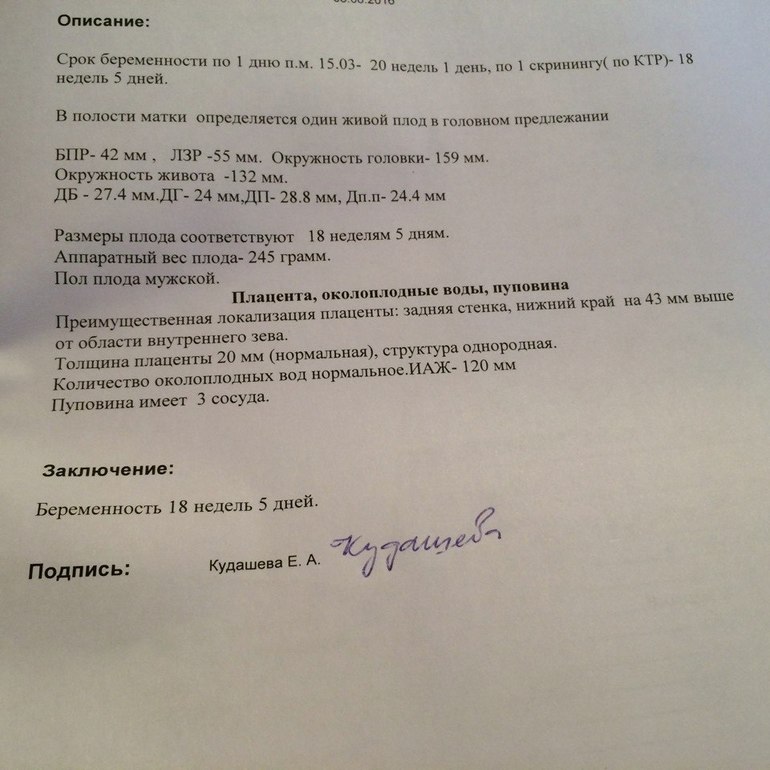

Слава Богу плацента моя поднялась хорошо....на 4,3 см) К слову к родам она должна быть на 5 см....так что думаю все хорошо)))) Шейка 47....тоже хорошая))))) Зайчонок лежал головкой вниз))))) Ну и приложу результаты фетометрии) вдруг кому интересно будет))))